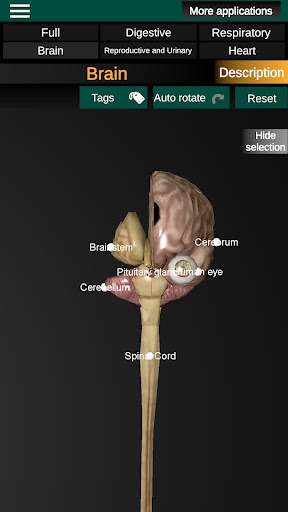

* Otak, yang meliputi otak, otak kecil, dan batang otak.